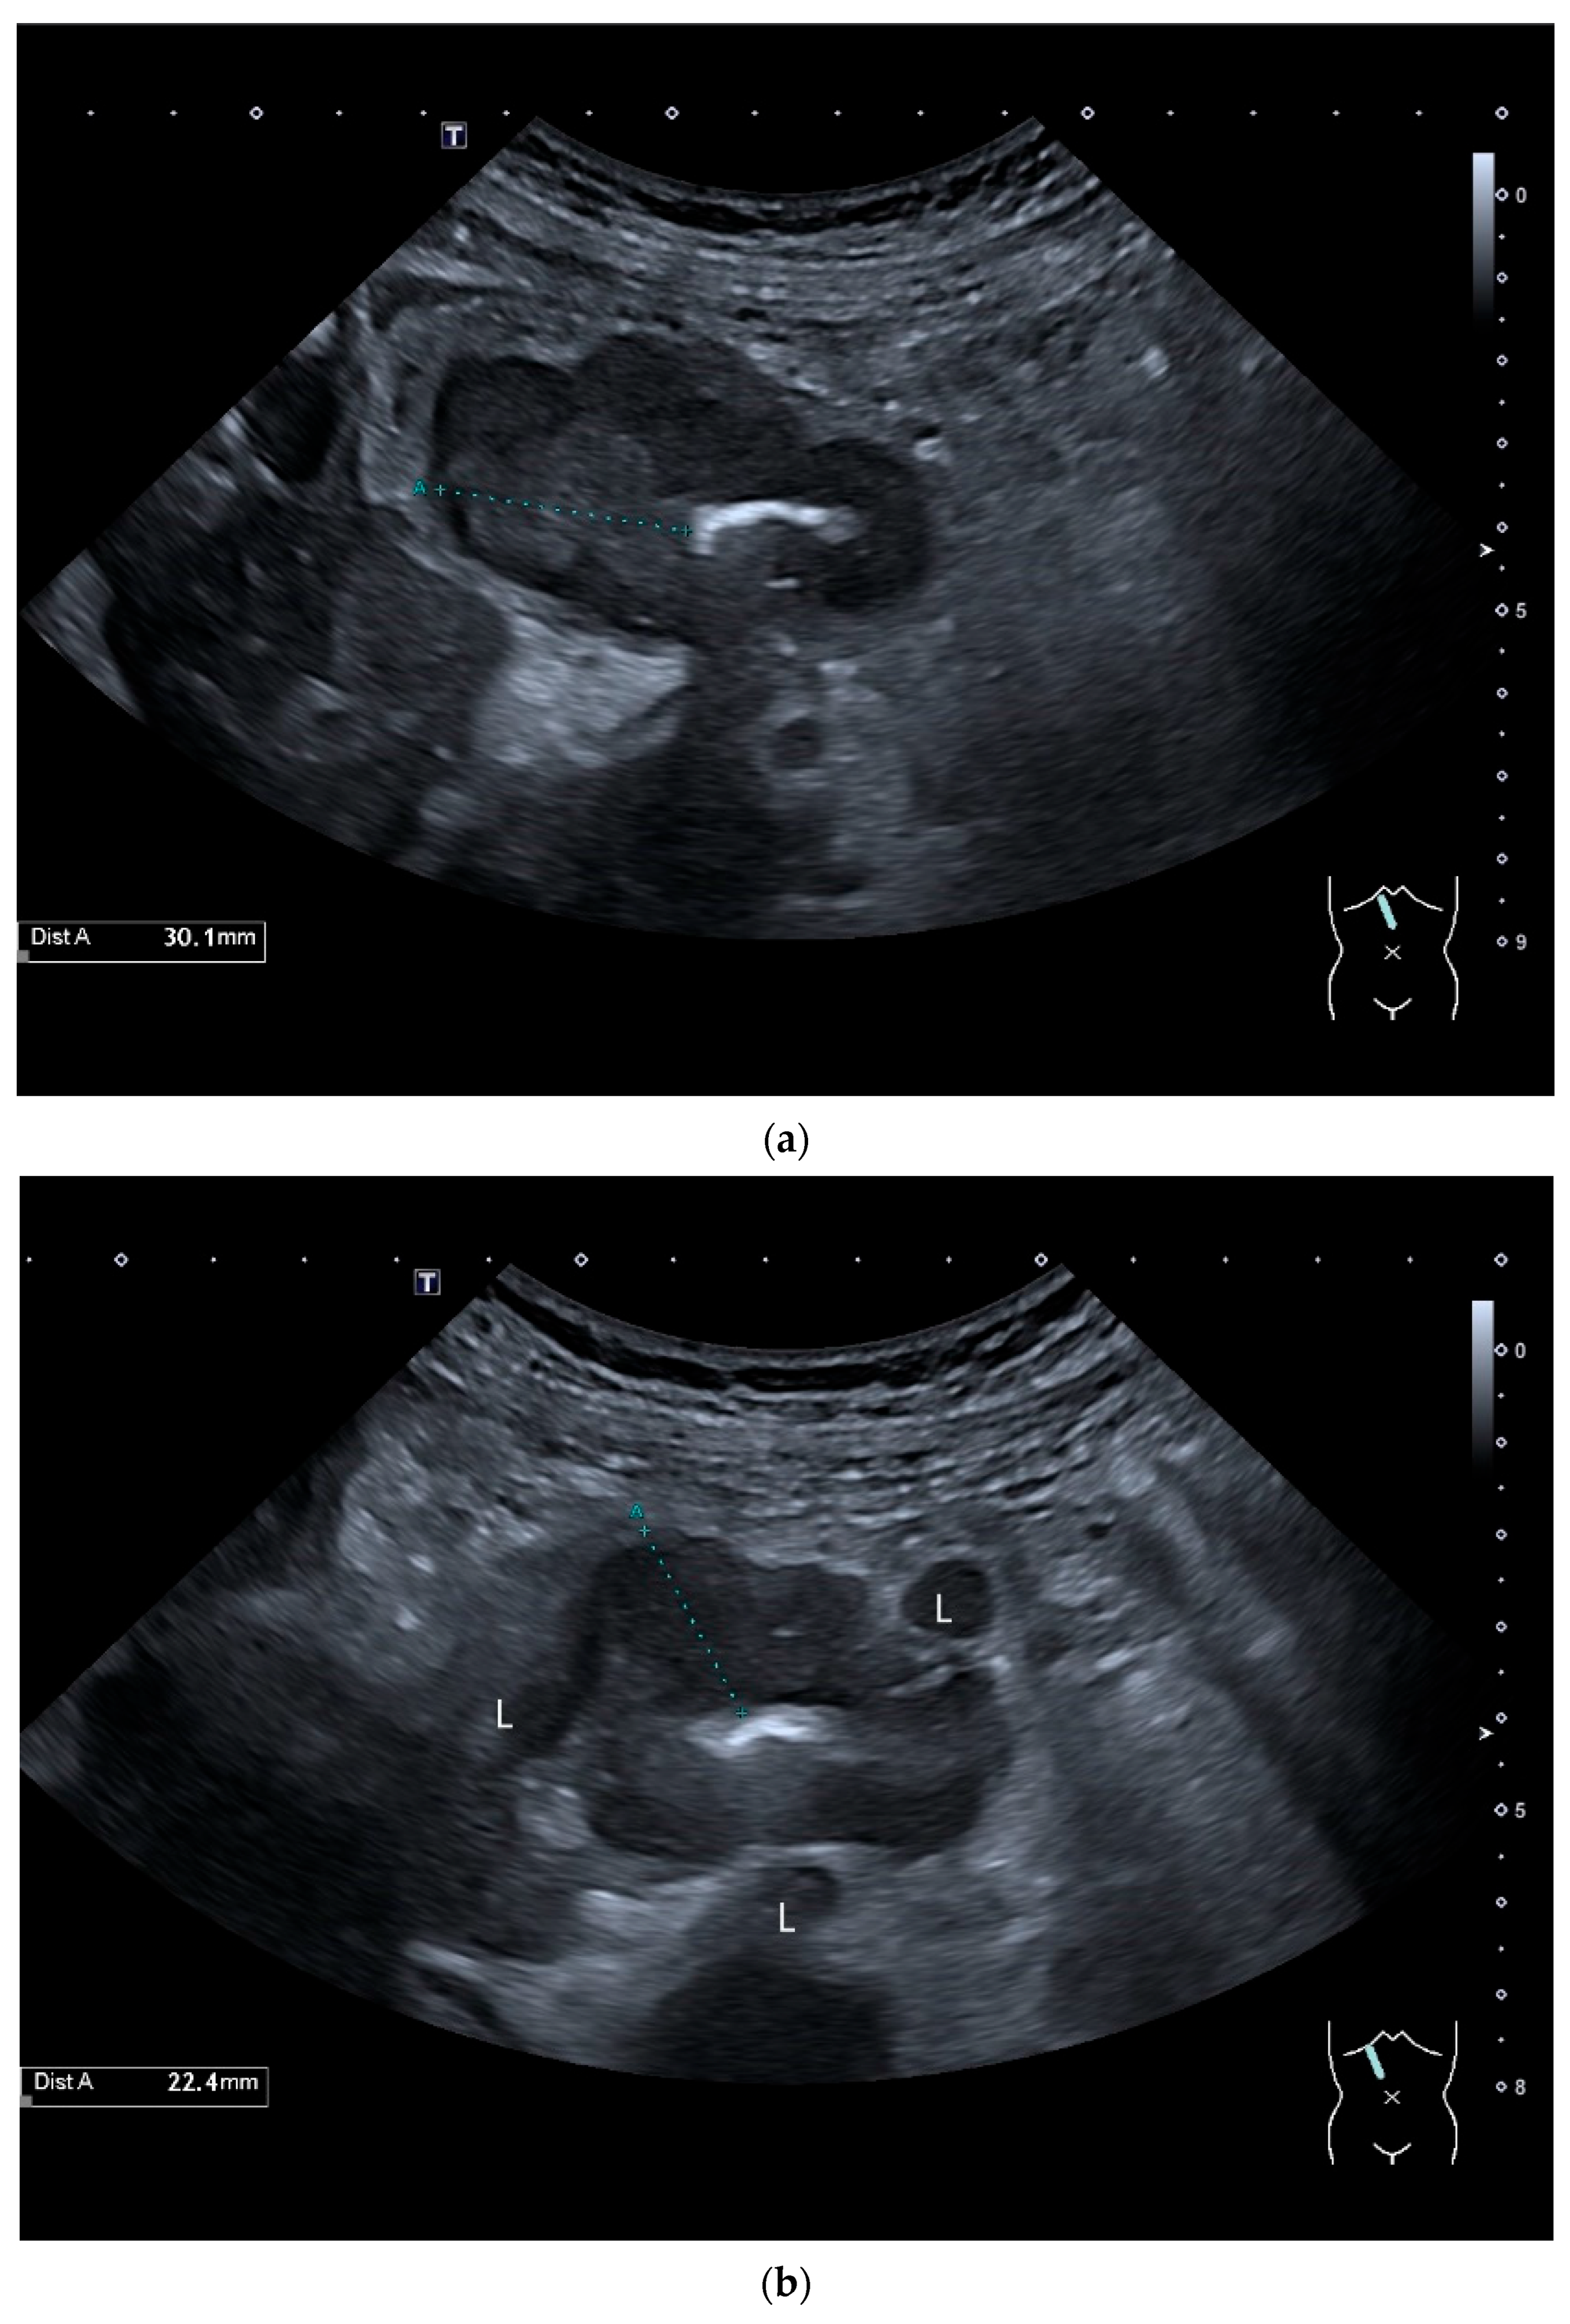

- Hasegawa, T.; Sumimura, J.; Mizutani, S.; Tazuke, Y.; Okuda, S.; Dezawa, T. The doughnut sign: An ultrasound finding in pediatric intestinal Burkitt’s lymphoma. Pediatr. Surg. Int. 1998, 13, 297–298. [Google Scholar] [CrossRef] [PubMed]

- Hasaballah, M.; Abdel-Malek, R.; Zakaria, Z.; Marie, M.S.; Naguib, M.S. Transabdominal ultrasonographic features in the diagnosis of gastrointestinal lymphoma. J. Gastrointest. Oncol. 2018, 9, 1190–1197. [Google Scholar] [CrossRef]

- Goerg, C.; Schwerk, W.B.; Goerg, K. Gastrointestinal lymphoma: Sonographic findings in 54 patients. Am. J. Roentgenol. 1990, 155, 795–798. [Google Scholar] [CrossRef]

- Zhang, X.Y.; Zhang, B.; Cai, S.; Jiang, Y.X.; Li, W.B.; Yang, X.; Zhao, R.N. Ultrasonographic and general pathologic features assessment of small intestinal lymphoma. Zhongguo Yi Xue Ke Xue Yuan Xue Bao 2013, 35, 318–321. [Google Scholar] [CrossRef]

- Cui, N.Y.; Gong, X.T.; Tian, Y.T.; Wang, Y.; Zhang, R.; Liu, M.J.; Han, J.; Wang, B.; Yang, D. Contrast-enhanced ultrasound imaging for intestinal lymphoma. World J. Gastroenterol. 2021, 27, 5438–5447. [Google Scholar] [CrossRef]

| Lymphoma | Very pronounced wall thickening with marked hypoechogenicity. Large regional and distant lymph nodes. Look for splenic infiltration. Tumor vessels on CDI and hyperenhancement on CEUS. Heterogeneous hyperechogenicity of the mesentery with walling of the mesenteric vessels. Multiple localizations are possible. |